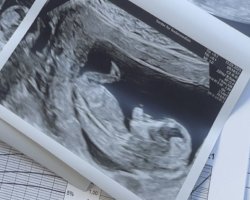

Sniker litt12+0 og alt så fint ut (enn så lenge). Veldig mye aktivitet, så var ikke lett å måle hjertefrekvensen «mye overskudd», sa jordmor

vil bare informere om at fullt navn og personnummer viser på bilde Vis vedlegget 456171